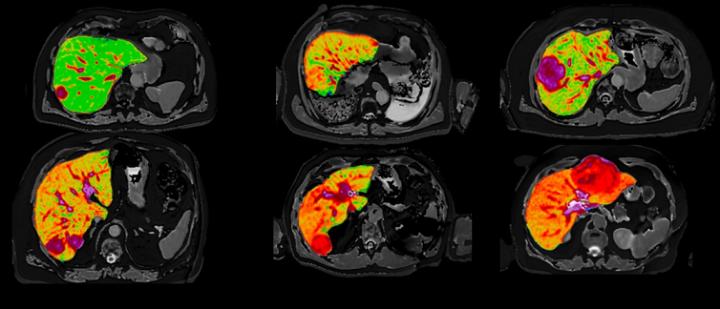

New Advances In Magnetic Resonance Techniques In Abdomen And Pelvis Magnetic Resonance Imaging Clinics